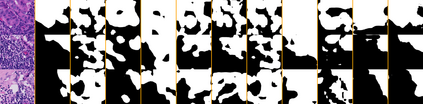

Weakly-supervised learning (WSL) has recently triggered substantial interest as it mitigates the lack of pixel-wise annotations. Given global image labels, WSL methods yield pixel-level predictions (segmentations), which enable to interpret class predictions. Despite their recent success, mostly with natural images, such methods can face important challenges when the foreground and background regions have similar visual cues, yielding high false-positive rates in segmentations, as is the case in challenging histology images. WSL training is commonly driven by standard classification losses, which implicitly maximize model confidence, and locate the discriminative regions linked to classification decisions. Therefore, they lack mechanisms for modeling explicitly non-discriminative regions and reducing false-positive rates. We propose novel regularization terms, which enable the model to seek both non-discriminative and discriminative regions, while discouraging unbalanced segmentations. We introduce high uncertainty as a criterion to localize non-discriminative regions that do not affect classifier decision, and describe it with original Kullback-Leibler (KL) divergence losses evaluating the deviation of posterior predictions from the uniform distribution. Our KL terms encourage high uncertainty of the model when the latter inputs the latent non-discriminative regions. Our loss integrates: (i) a cross-entropy seeking a foreground, where model confidence about class prediction is high; (ii) a KL regularizer seeking a background, where model uncertainty is high; and (iii) log-barrier terms discouraging unbalanced segmentations. Comprehensive experiments and ablation studies over the public GlaS colon cancer data and a Camelyon16 patch-based benchmark for breast cancer show substantial improvements over state-of-the-art WSL methods, and confirm the effect of our new regularizers.